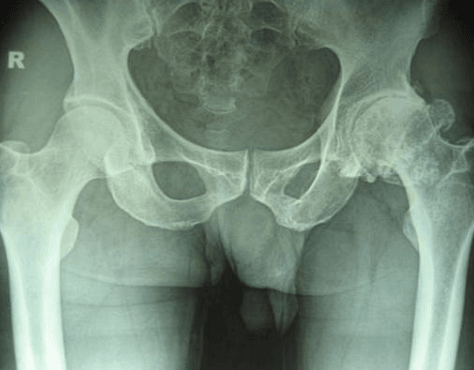

Chẩn đoán bệnh thoái hóa khớp háng

Để chẩn đoán được chính xác về bệnh thoái hóa khớp háng, bác sĩ sẽ kết hợp kiểm tra về các triệu chứng và tiền sử bệnh cùng với các xét nghiệm chẩn đoán, chẳng hạn như chụp X-quang.

Kiểm tra hình ảnh

Chụp X-quang khớp háng có thể cho thấy không gian khớp bị thu hẹp, các thay đổi trong xương và sự hình thành các gai xương (các tế bào xương).

Các xét nghiệm hình ảnh khác. Đôi khi, chụp cộng hưởng từ (MRI) hoặc chụp cắt lớp vi tính (CT) có thể cần thiết để xác định rõ hơn tình trạng của xương và các mô mềm ở hông.